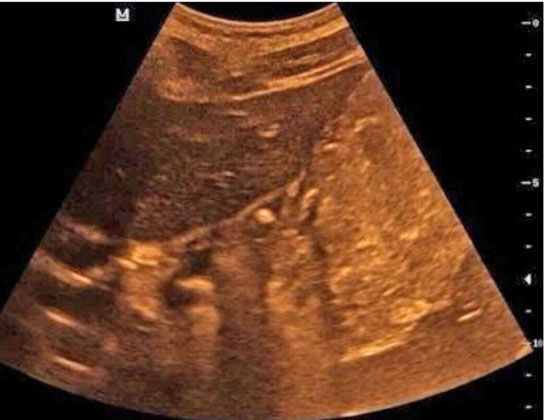

胃肠超声显示小英胃的贲门口位置有一个大约5mm的溃疡

就在这时,有朋友给小英的妈妈推荐了胃肠超声检查。按照约定的时间,小英一大早就空腹来到齐鲁医院青岛院区健康管理中心,喝下了医生为她特制的“黑芝麻糊”后,B超室医生为她进行了胃肠超声检查,结果发现小英胃的贲门口位置有一个大约5mm的溃疡,与她疼痛的位置相符。